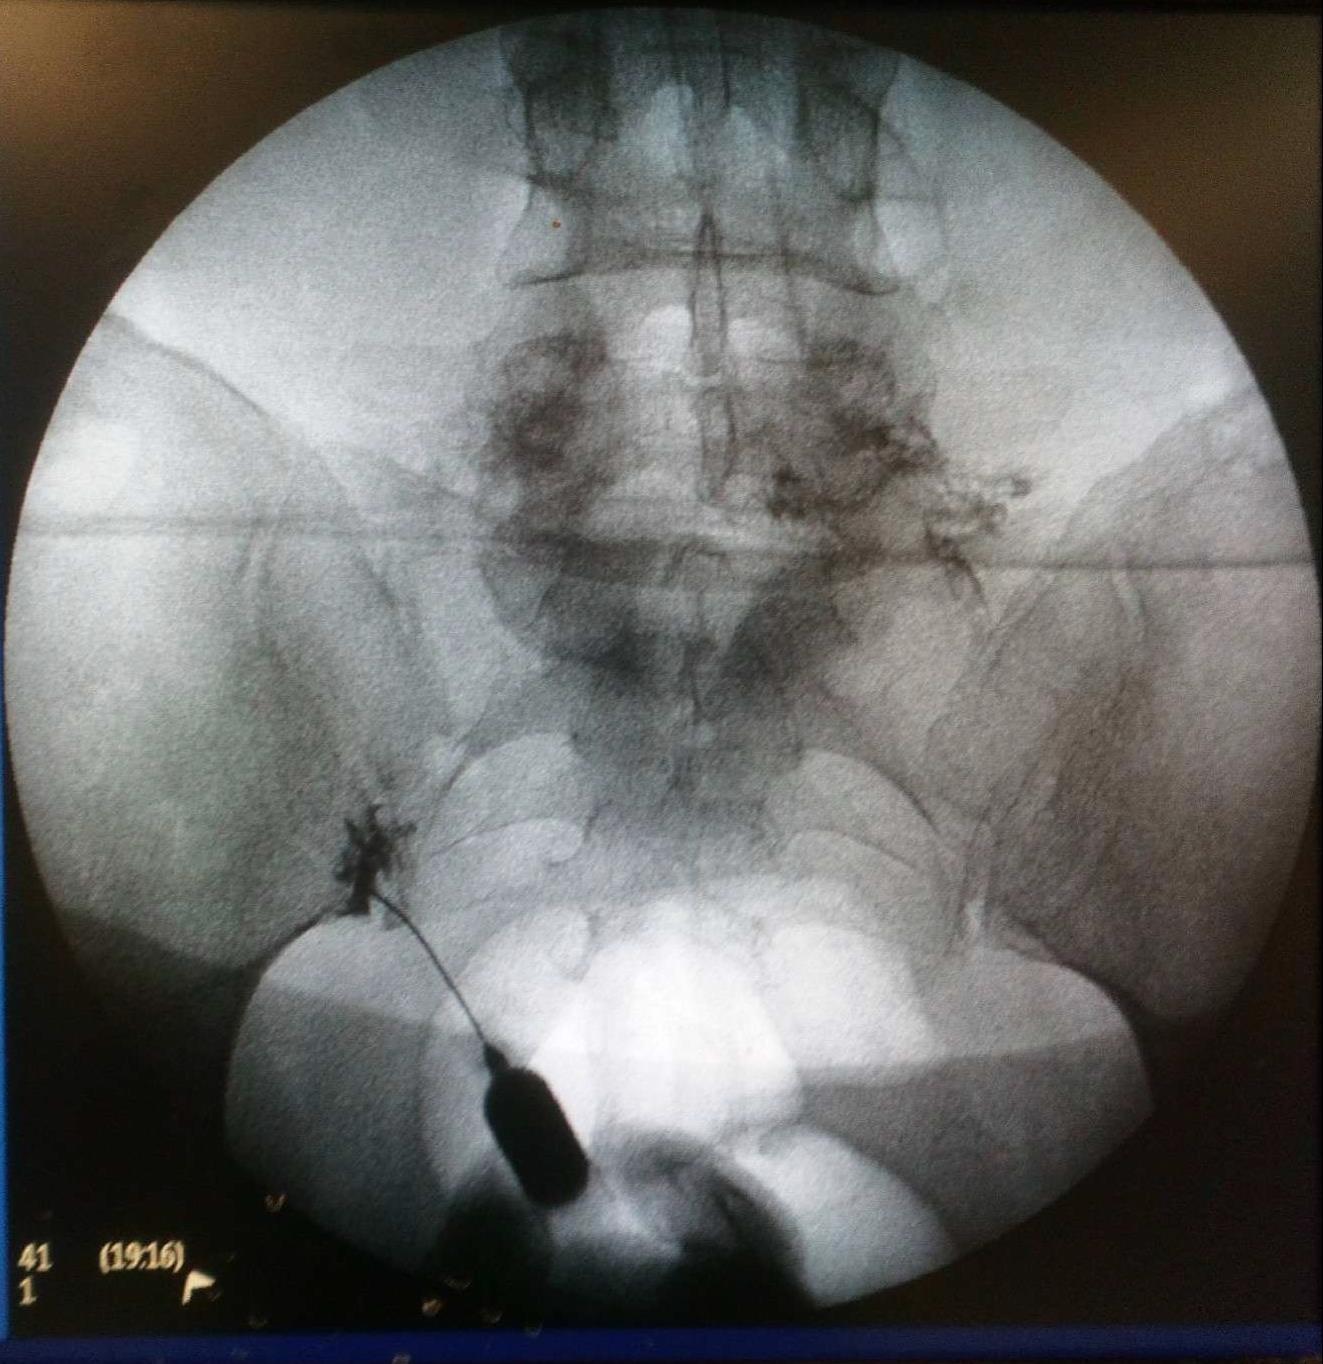

Ασθενής με σπονδυλαρθρίτιδα και 2 δισκοκήλες

Ασθενής 86 ετών με έντονο άλγος οσφύος, αντανάκλαση στο κάτω άκρο και αιμωδίες αριστερού άκρου ποδός απο 2μήνου λόγω σπονδυλαρθρίτιδας και 2 δισκοκηλών σε 2 επίπεδα. Με τοπική αναισθησία τοποθέτηση 2 βελόνων.  Έλεγχος σωστής τοποθέτησης με χρήση σκιαστικού και εισαγωγή μείγματος αναλγητικών. Άμεση ανακούφιση με αποτέλεσμα που διατηρείται 1.5 χρόνο μετά.